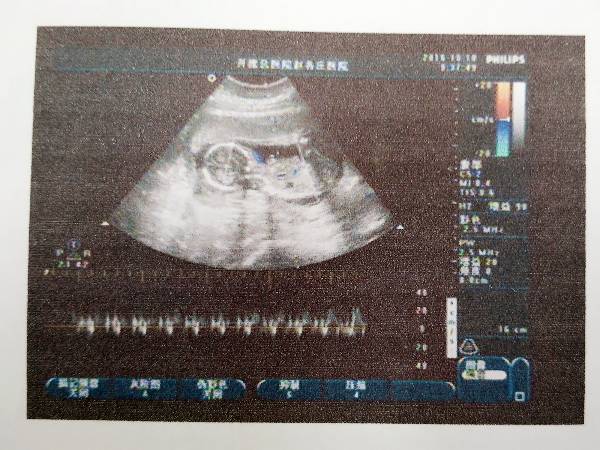

能看出是男宝还是女宝么,很好奇,而且宝宝用品衣服也不知道往哪儿个 能看出是男宝还是女宝么,很好奇,而且宝宝用品衣服也不知道往哪儿个方向买,大夫根本不说,塞钱又给塞回来了 点击展开 匿名用户 2016-10-22 12:14 推荐回答 其实你看胎心率是看不出典射截他高做性别的,想要知道胎儿性别的辨过话,需要直接做B超的时候管看见的话才可以检查得比较准确。 楚浩瀚_ma9p 2016-10-22 12:50 宝宝知道提示您:回答为网友贡献,仅供参考。 相关问题 听说有人会通过b超单看出是男宝还是女宝,有点好奇,看看怀孕8周左右,孕囊3 7×1 7×4 5cm是男宝宝还是女宝宝?? 八周加五天孕囊38×17×37是男宝还是女宝 好奇心呢 男女都是宝 我的肚子有点像倒三角,是男宝还是女宝呢?!很好奇